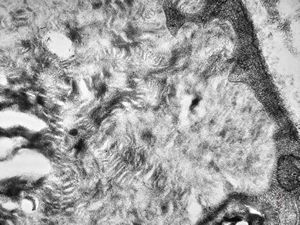

M,3y. | globoid leukodystrophy of Krabbe - n.suralis

M,3y. | globoid leukodystrophy of Krabbe - n.suralis

M,3y. | globoid leukodystrophy of Krabbe - n.suralis

M,3y. | globoid leukodystrophy of Krabbe - n.suralis

M,3y. | globoid leukodystrophy of Krabbe - n.suralis